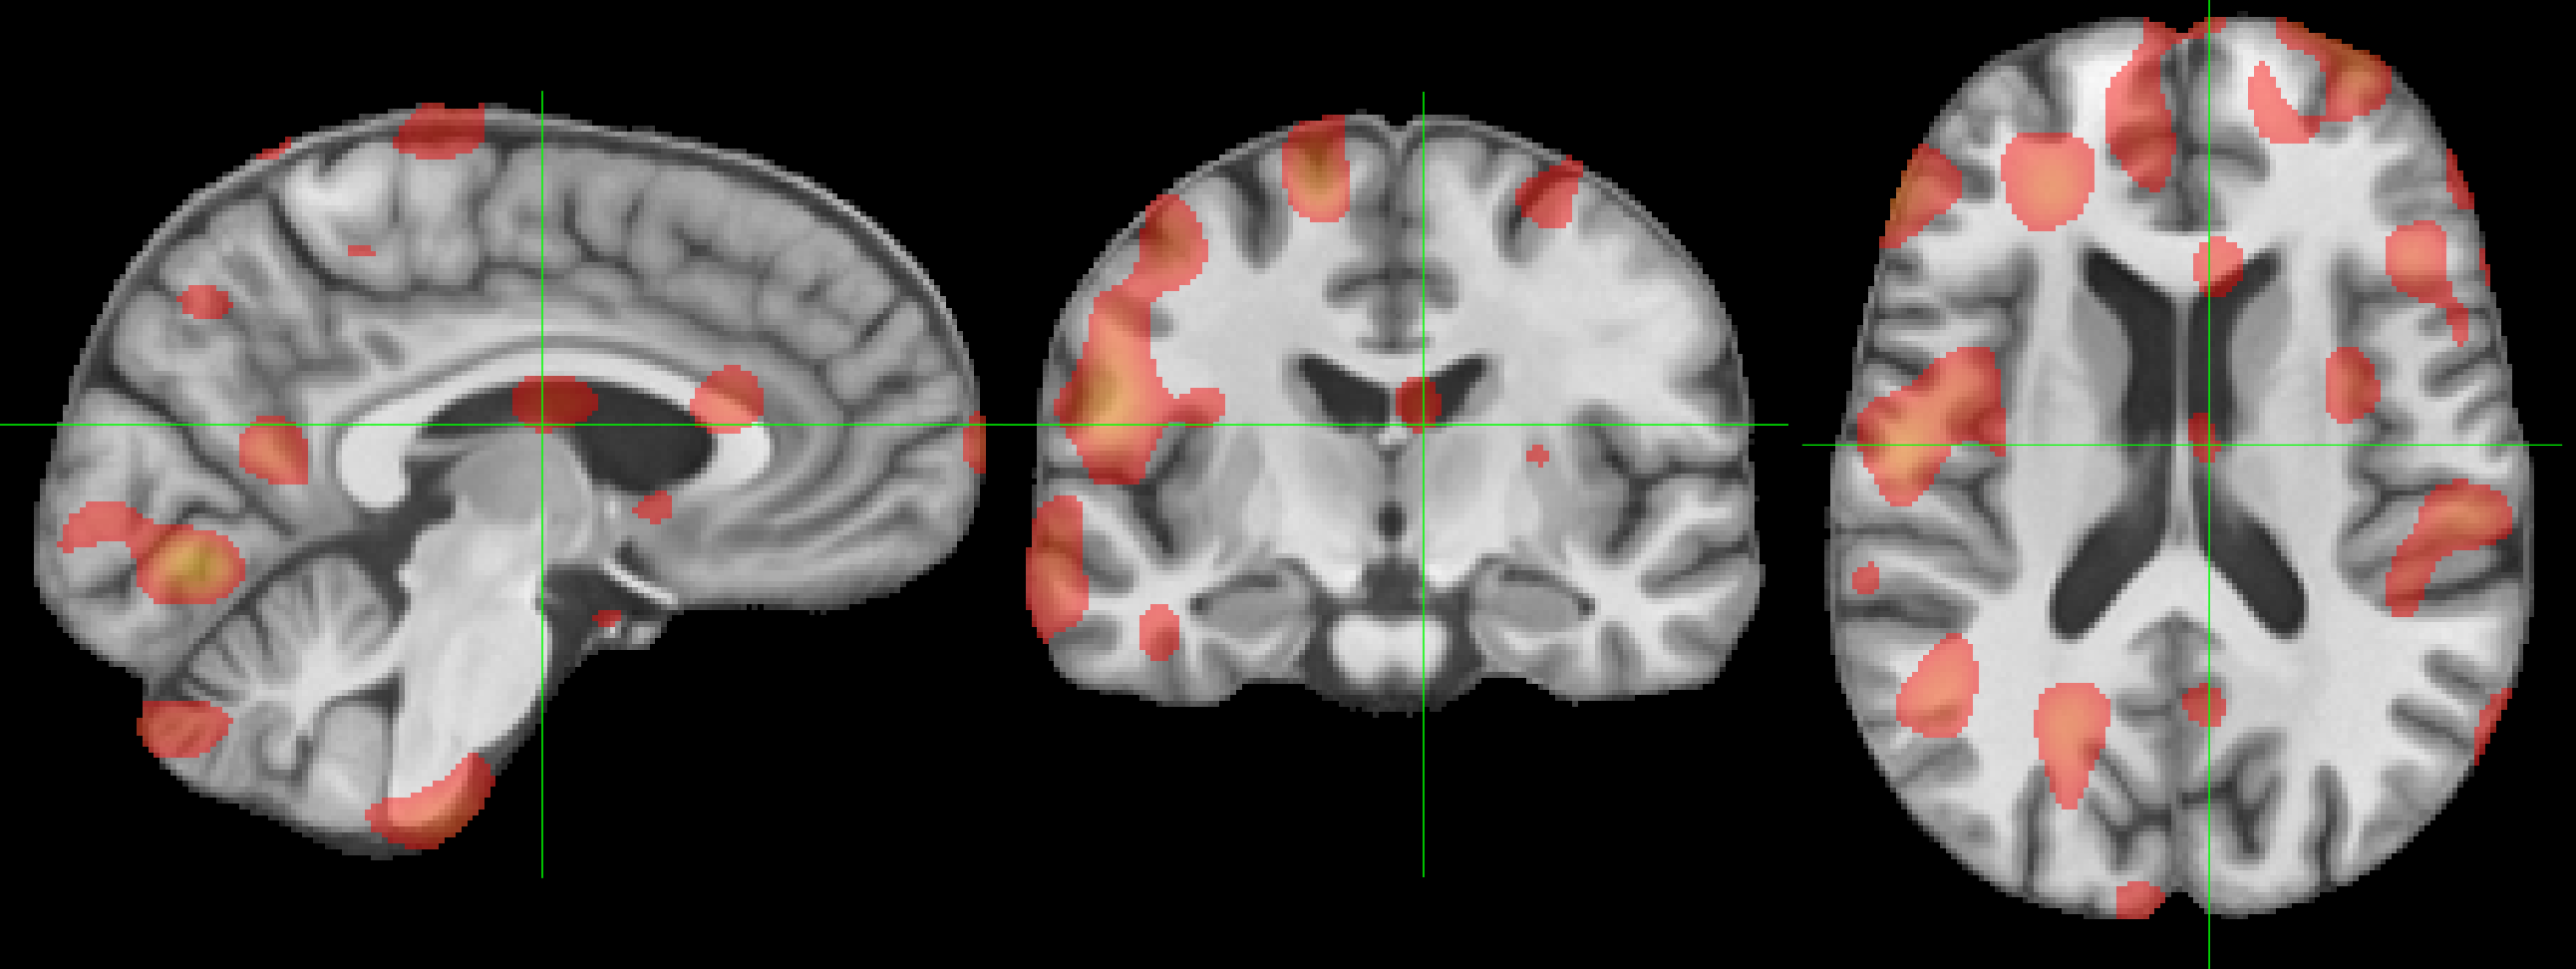

Refer to caption

(a) Base NiT Attention Map

(b) MINiT Attention Map

Refer to caption \phantomcaption

Figure 6: Attention maps learned by (a) NiT and (b) MINiT models. The bar shows the color-map (from red =0.4absent0.4=0.4 to yellow =0.8absent0.8=0.8; thresholded on the lower bound for clarity).

We compute the attention maps for the base NiT from the output token to the input space using Attention Rollout [1]. For MINiT, we use Attention Rollout to calculate attention weights for each patch in a block, which we concatenate and then average to build attention weights for a block. We proceed to use Attention Rollout using the block attention weights to compute the final attention maps. From Fig. 6, we observe that MINiT attends between numerous different voxels in the neuroimage (due to MIL nature), in contrast to the focused attention between fewer, but larger, voxels by the base NiT. Considering existing documented evidences [21] that sex differences in youth are widespread in the brain and the significant difference in accuracy between the two models, it is evident that MINiT is able to better generalize by capturing features spread all around the brain.